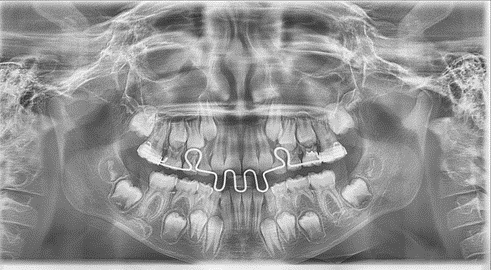

Медицинские Исследования: Кортикальная Пластинка на ОПТГ